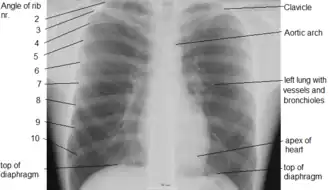

X-ray image of the human chest showing the internal anatomy of the rib cage, lungs and heart as well as the inferior thoracic border–made up of the diaphragm.

An X-ray of a human chest area, with some structures labeled

The contents of the thorax include the heart and lungs (and the thymus gland); the major and minor pectoral muscles, trapezius muscles, and neck muscle; and internal structures such as the diaphragm, the esophagus, the trachea, and a part of the sternum known as the xiphoid process. Arteries and veins are also contained – (aorta, superior vena cava, inferior vena cava and the pulmonary artery); bones (the shoulder socket containing the upper part of the humerus, the scapula, sternum, thoracic portion of the spine, collarbone, and the rib cage and floating ribs).